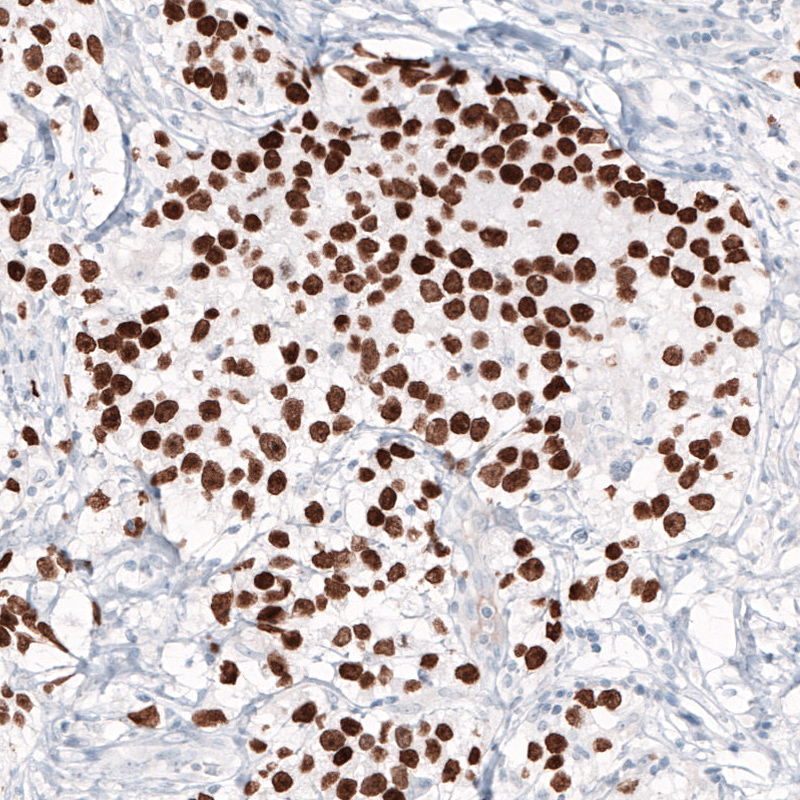

Immunohistochemical staining of human testis cancer shows strong nuclear immunoreactivity in tumor cells.